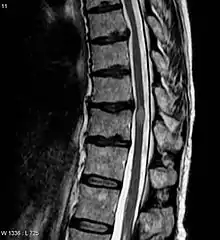

![]() | |

| An MRI showing a transverse myelitis lesion, which is lighter, oval shape at center-right. The patient recovered 3 months later. | |